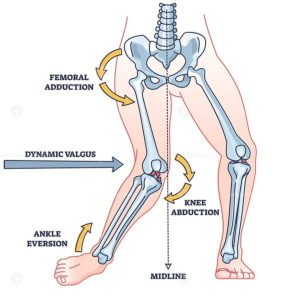

رباط صلیبی قدامی یکی از چهار رباط اصلی زانو است که استخوان ران (فمور) را به ساق پا (تیبیا) متصل میکند. وظیفهی اصلی آن، جلوگیری از جابهجایی قدامی تیبیا نسبت به فمور و کنترل حرکات چرخشی زانو است. این رباط در فعالیتهایی که با پرش، چرخش یا توقفهای ناگهانی همراه هستند، آسیبپذیرتر است.

- تغییر مسیر یا چرخش ناگهانی هنگام دویدن

- فرود نامناسب پس از پرش

- توقف یا کاهش سرعت ناگهانی